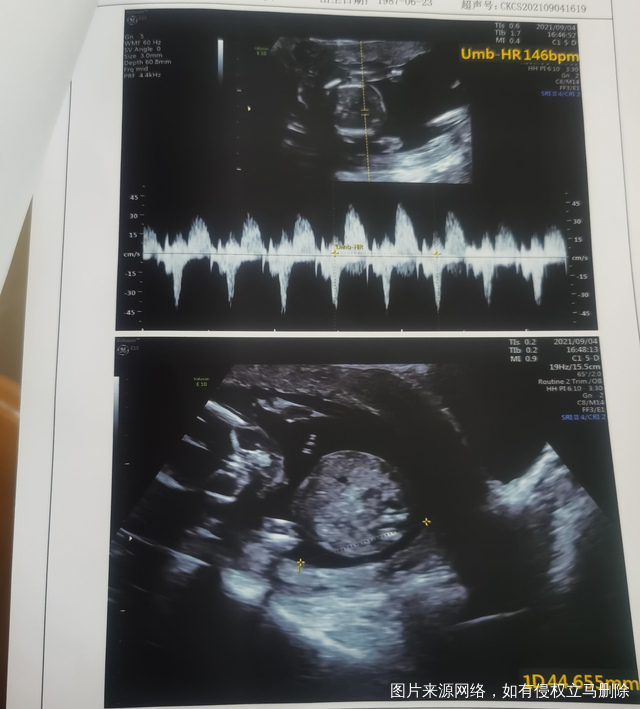

今天是怀孕16周去做了胎心监测还有做了一个B

正常的胎盘附着于子宫体部的前壁、后壁或侧壁,远离宫颈内口。妊娠28周后,胎盘仍附着于子宫下段,其下缘达到或覆盖宫颈内口,位置低于胎儿先露部,称为前置胎盘。你的情况,现在孕周还小,还不能确定是前置胎盘。遵医嘱用药吧!注意休息,观察是否有阴道流血,如果有阴道流血,及时去医院。